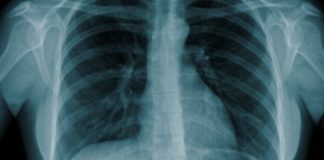

Saúde Pública tranquiliza sobre caso de tuberculose em escola

As autoridades de Saúde Pública garantem que o caso de tuberculose, diagnosticado a um aluno do Agrupamento de Escolas de Pombal, está controlado pelo...